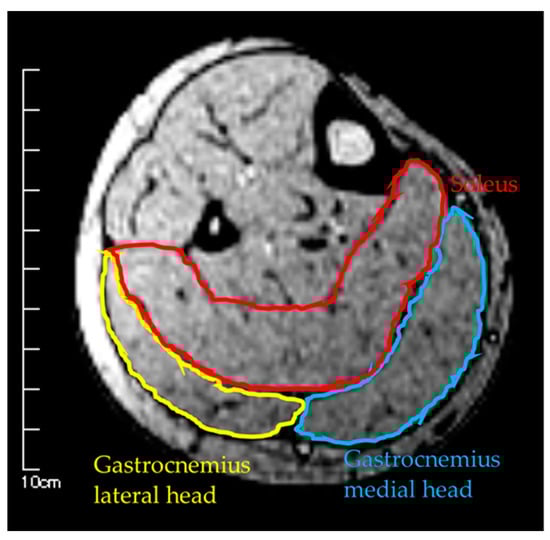

Figure 2.

Measurement of muscle cross-sectional area by MRI.

Measurements were taken in three conditions: (1) MRI in the supine position, (2) MRI in the sitting position, and (3) US imaging in the sitting position. The sitting position was chosen for the measurement of the antigravity position because it is easy to hold the limb position with little motion in the antigravity position. In the supine position for MRI, the foot was placed on a pedestal in a supine position in which the hip and knee joints were flexed at 90°, and the foot was supported only by the heel to prevent the triceps surae from changing its shape due to contact with the pedestal. In addition, a plate was placed perpendicular to the floor at the plantar part of the foot to maintain dorsiflexion at 0°. MRI and US imaging in the sitting position were performed in a chair (with a backrest) with the knee joint flexion at 90°, the lower leg perpendicular to the floor, and the ankle joint dorsiflexion at 0° as in the supine position. In all measurements, the thigh was fixed with cushions and bands to prevent the lower leg from moving during the imaging, and the participants were instructed to hold it as much as possible. Using vertical MRI with a 0.4 T permanent magnet, (Hitachi Healthcare, Ltd., Tokyo, Japan), horizontal T1-weighted images were obtained from the fibular head to the 290 mm distal end at 10 mm intervals (Figure 1). The imaging parameters were as follows: slice plane axial; pulse sequence RF-spoiled steady-state gradient echo; field of view, 280 mm; repetition time, 110.0 ms; echo time, 8.6 ms; flip angle, 35°; slice thickness, 10.0 mm; slice interval, 10.0 mm; matrix size, 256 × 256; number of signals, average of 2; receiver bandwidth, 20.6 kHz; and scan time, 4 min and 32 s. Using the image analysis program ZedView (LEXI Co., Ltd., Tokyo, Japan), the muscles were identified based on the boundary of the fascia of the soleus (SOL), gastrocnemius medial head (GM), and gastrocnemius lateral head (GL) using the acquired images, and the areas marked on the images were measured as the MCSA of each muscle (Figure 2). The 10 mm slice areas of MRI were summed, and the volume of each muscle was calculated using a ZedView. The images of the SOL, GM, and GL were taken by US using a linear probe (7.5 MHz) in B-mode MyLab25 (Esaote, Florence, Italy). Short-axis images were taken at 20.0 mm intervals from the peroneal head in each muscle by applying a probe to the center of the ventral region of the muscle on the horizontal plane. We used a hard-type gel (LOGIQLEAN, GE Healthcare Japan, Tokyo, Japan), which is flexible and easy to keep in shape, to avoid direct contact between the probe and the lower leg. Indirect contact through the gel avoids the effects of pressure exerted by the probe on the lower leg. In addition, to maintain the position of the probe at the time of measurement, we marked the lower leg prior to the measurement, following which assessments were made based on the marking. For the measurement of MT, the maximum length of each muscle was measured with respect to the boundary of the fascia using the image analysis program Image J (Figure 3). The average value of the two measurements was calculated and used as the MT value. MRI, US imaging, and MCSA and MT measurements were performed by the same examiner.